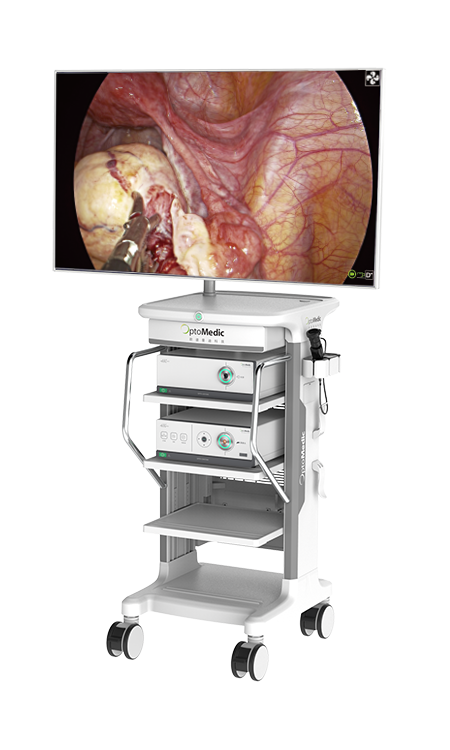

GYNECOLOGICAL SURGERY

HEPATOBILIARY SURGERY